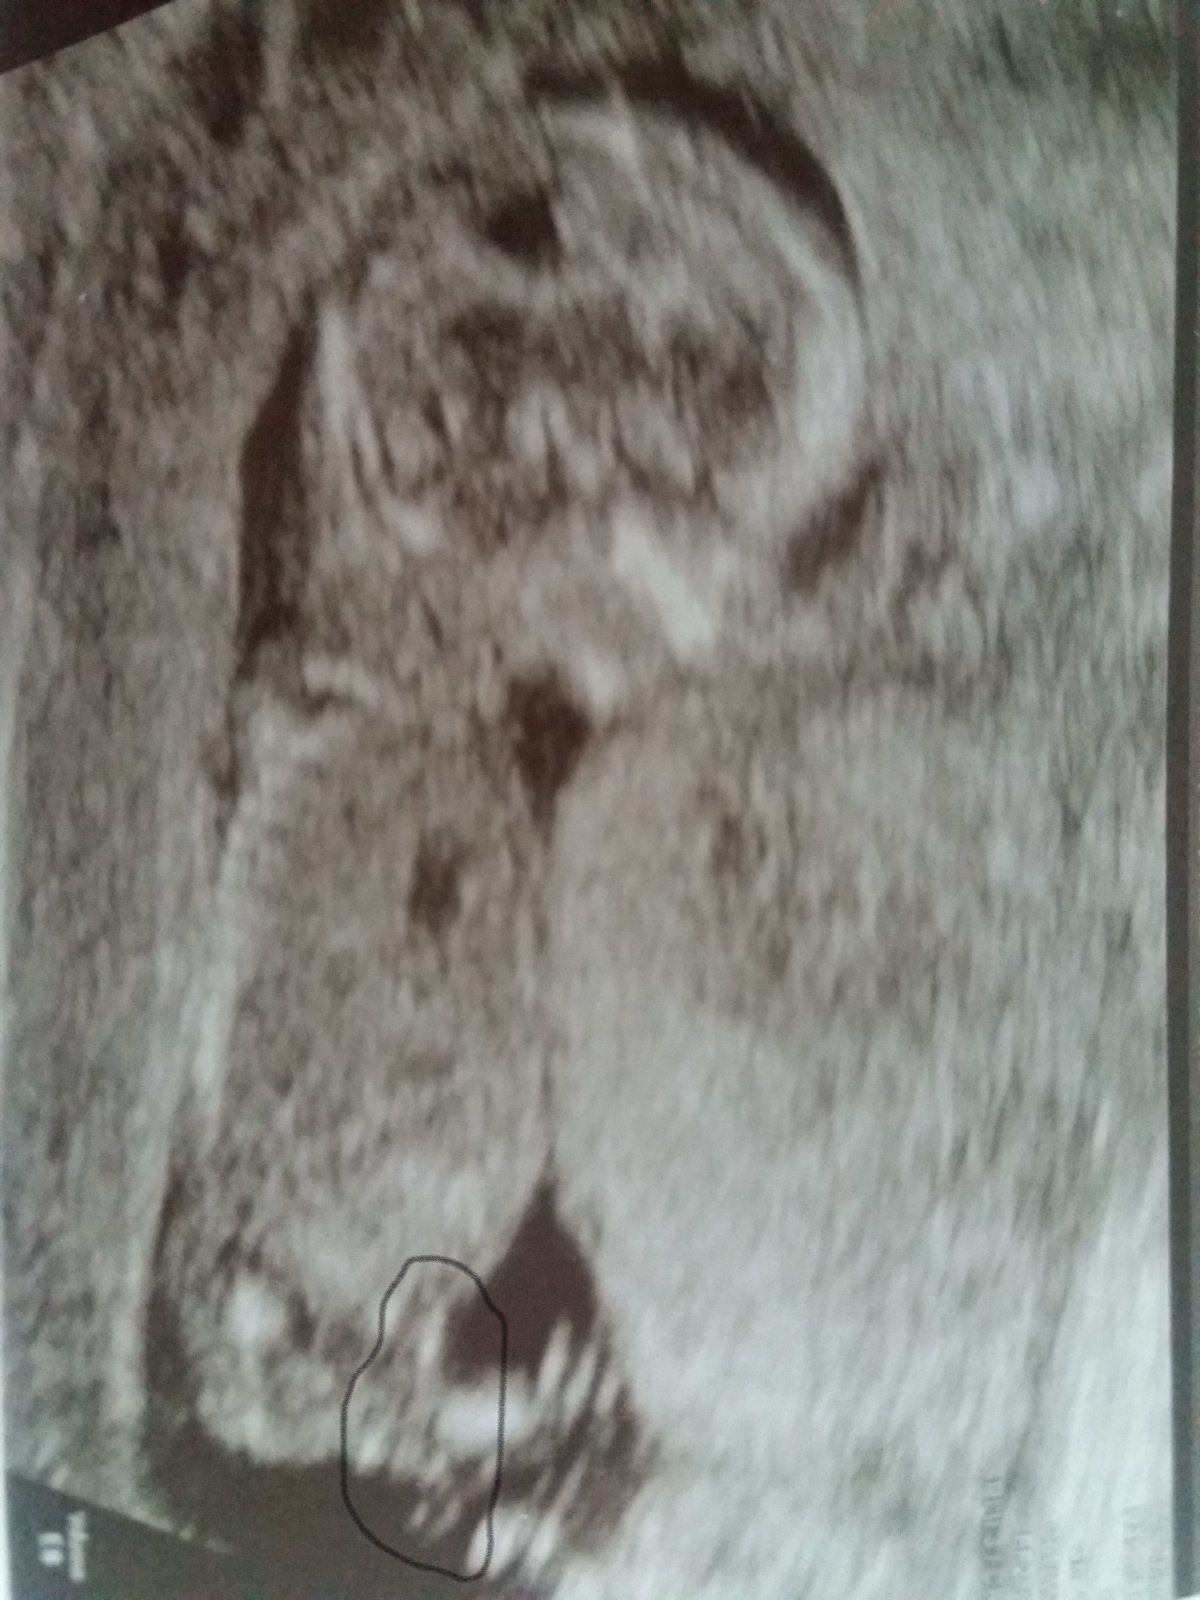

Přikládám foto ultrazvuku holčičky v 16tt pro ostatní maminky pro porovnani, je to zaber zespodu jakoby na prdku s roztazenyma nozkama 😉.

@mikejla_a ta tenká čárka v pravo dole by měl být pohl. hrbolek co směřuje nahoru 🙂

@fiendish.angel pokud je to za nožičkou pohlaví hrbolek tak by to měla týt holčička

@kristyna14092013 holčička. pohlavní hrbolek je souběžně s osou páteře. kdydy výrazně čněl nahoru, je to kluk 🙂